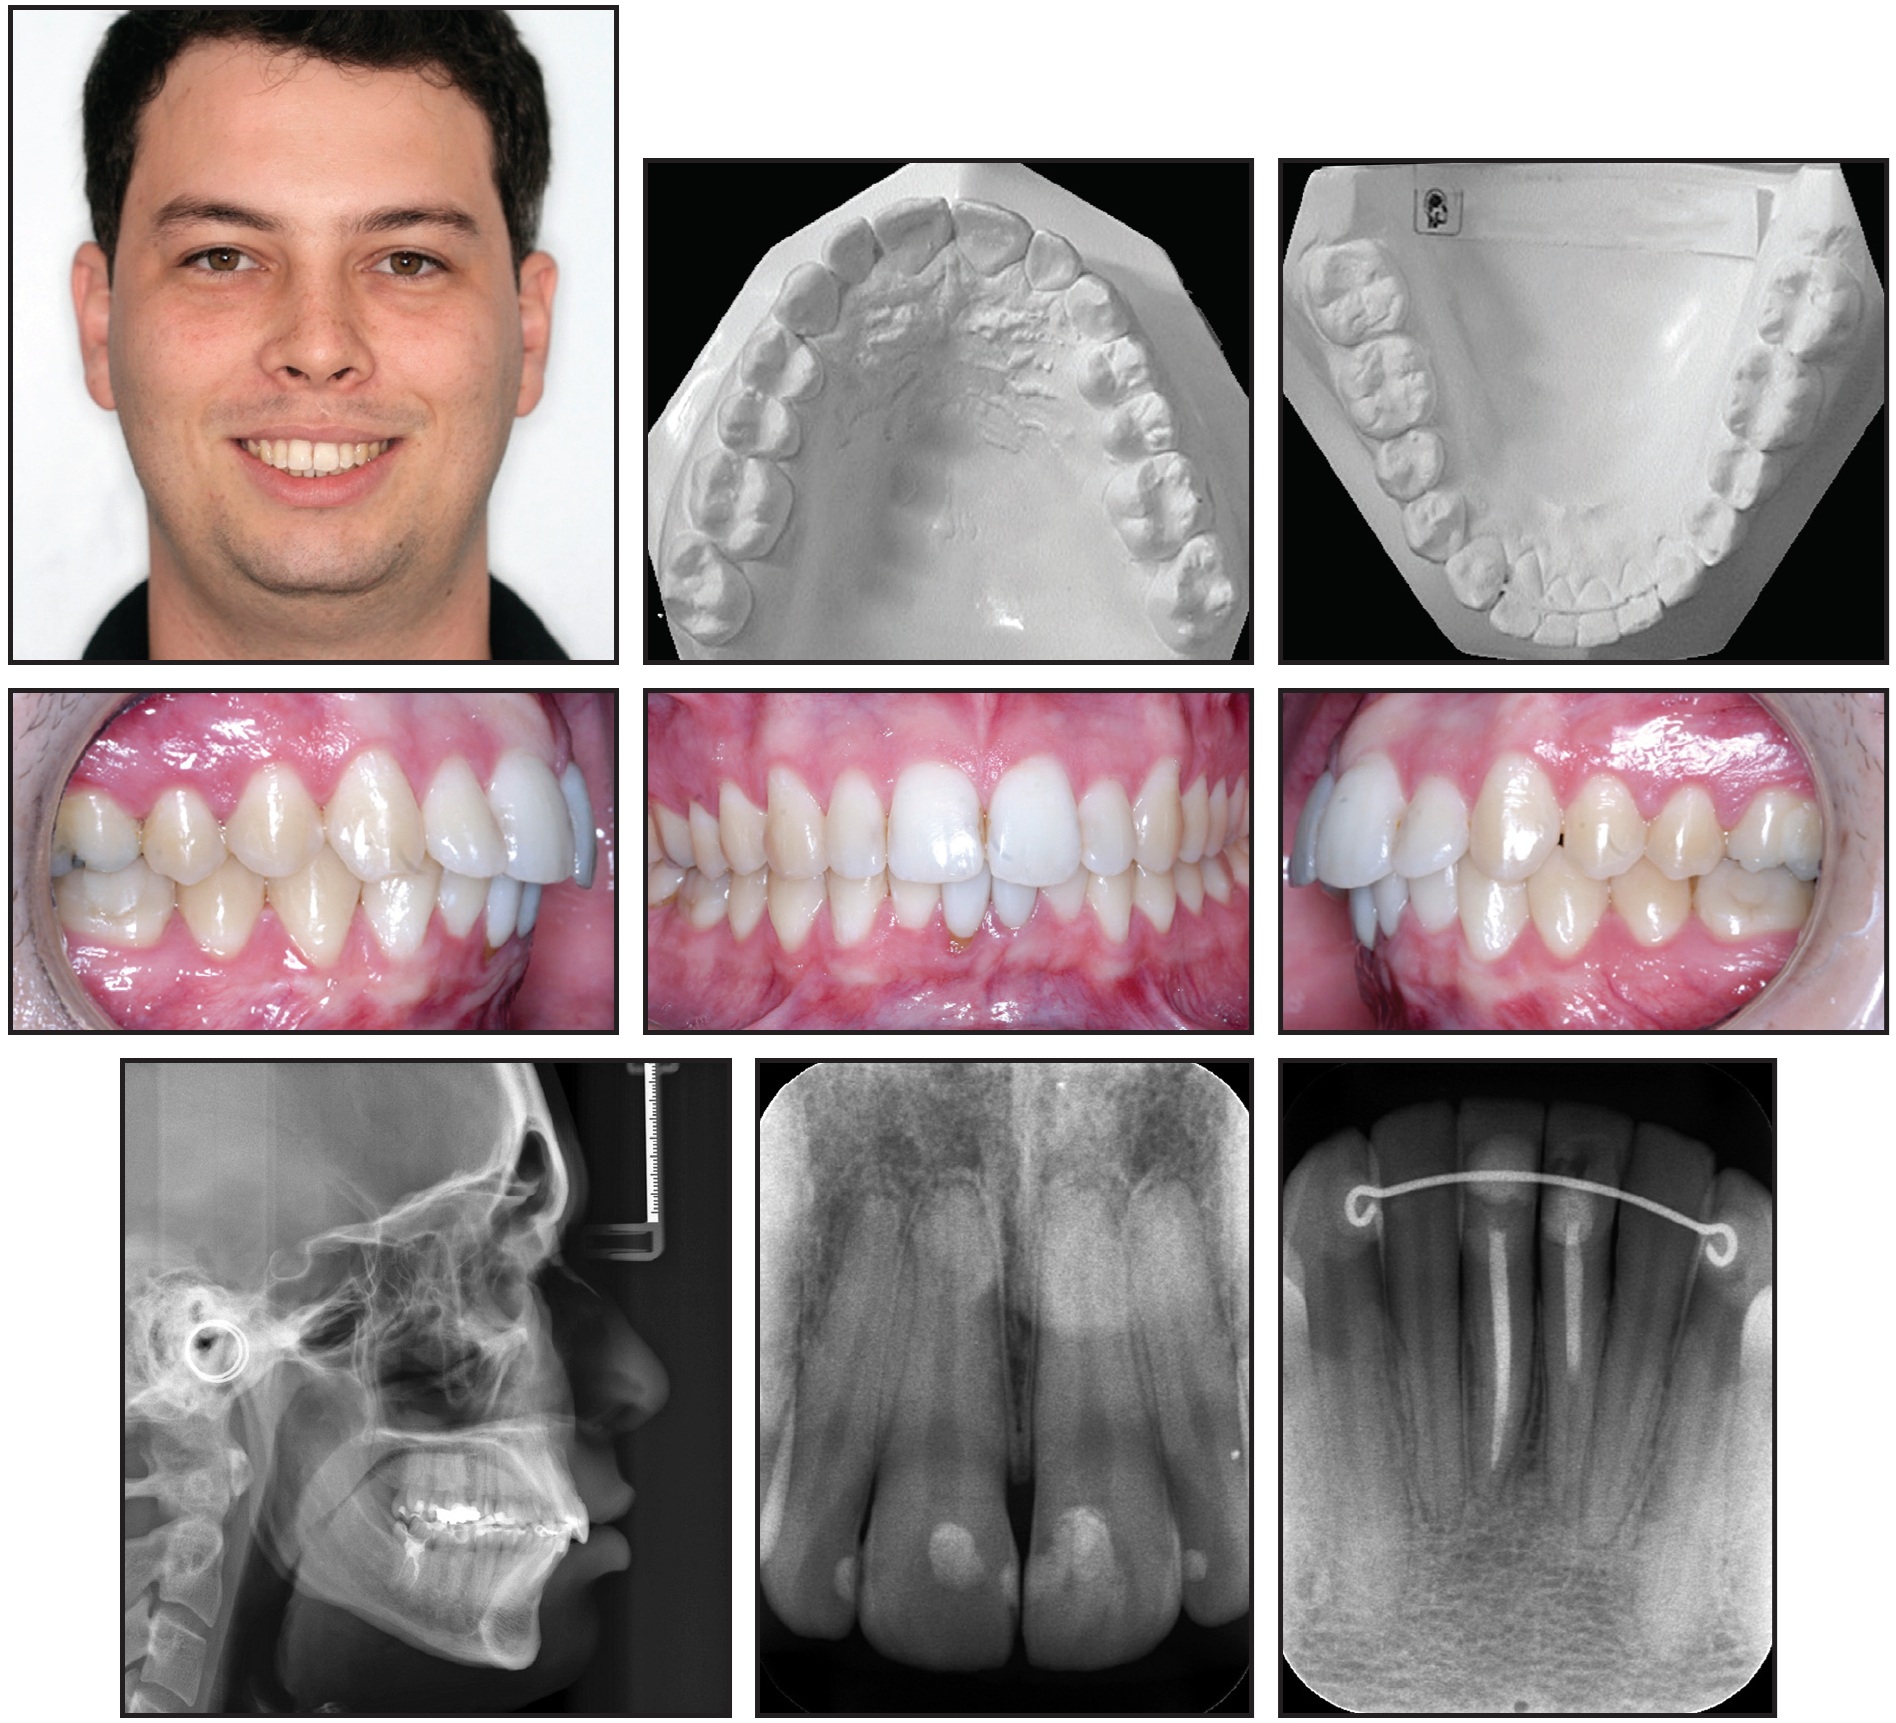

A 25-year-old male presented with the chief complaint of crowding in the mandibular anterior segment, including a complete lack of space for two mandibular incisors (Fig. 1A). He exhibited a balanced facial profile, Class I molar and canine relationships, somewhat narrow maxillary and mandibular arches, crowded upper incisors, and severely crowded lower incisors (Fig. 1B).

Fig. 1 25-year-old male patient with lower anterior crowding, Class I molar and canine relationships, skeletal Class II relationship, and severe overbite and overjet before treatment (continued in next image).

Fig. 1 (cont.) 25-year-old male patient with lower anterior crowding, Class I molar and canine relationships, skeletal Class II relationship, and severe overbite and overjet before treatment.

Cephalometric analysis indicated a Class II skeletal relationship with a slightly protrusive maxilla and a slightly retrusive mandible (Table 1). The overjet and overbite were extreme because of the lower crowding. The maxillary incisors were vertically inclined and slightly retrusive, while the mandibular incisors were labially inclined and protrusive. The nasolabial angle was within the normal range. A panoramic radiograph confirmed the absence of the third molars, which had been extracted previously.

Total treatment time was 35 months (Fig. 5). The balanced profile and Class I canine and molar relationships were successfully maintained, and the patient was highly satisfied with his teeth and profile. The mandibular incisors were aligned, with the proper torque. The skeletal maxillomandibular relationship was slightly improved, the maxillary incisors were slightly proclined, and the mandibular incisors were uprighted (Table 1). The overjet and overbite were reduced, and the upper and lower lip positions and nasolabial angle were basically unchanged.

Fig. 5 Patient after 35 months of treatment (records taken seven months later).